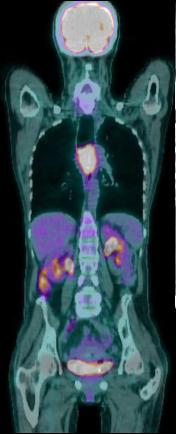

Image PET /CT en coupe

coronal ( frontale ): . Tumeur epidermoide 1/3 moyen

de oesophage avec metastase du foie , reins ,

ganglion pelvienne . et des os ... ( bilan

d'extention metastasique ) |